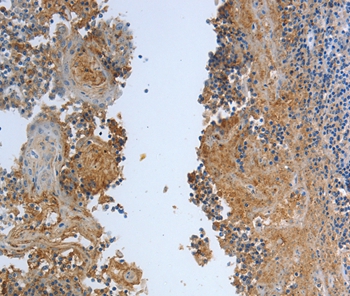

Immunohistochemical analysis of paraffin-embedded Human tonsil tissue using #37222 at dilution 1/30.

应用详情:Immunohistochemistry: 1:25-1:100